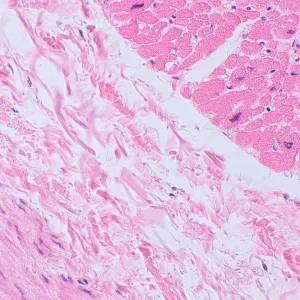

С помощью микроскопа MAGUS Bio 250TL изучают тонкие срезы и мазки биологических образцов. Исследования ведутся в светлом поле в проходящем свете. В качестве осветителя выступает 3-ваттный светодиод, а оптика включает планахроматические объективы, рассчитанные на бесконечность. Микроскоп поддерживает установку дополнительных аксессуаров, в том числе устройств для работы по методам темного поля, поляризованного света и фазового контраста. Этот микроскоп – идеальный выбор для лабораторной диагностики, научных исследований и обучения.